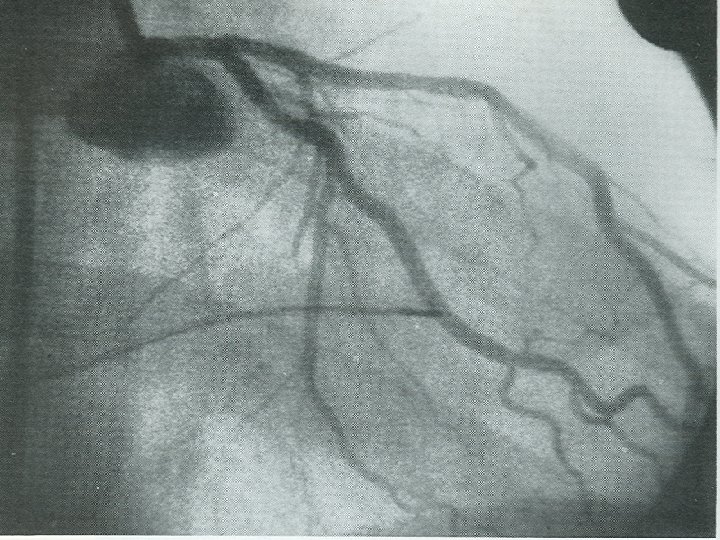

The first coronary angioplasties in Zurich • Stiff wire with a C-shaped tip introduced

The first coronary angioplasties in Zurich • Stiff wire with a C-shaped tip introduced through a plastic catheter (arrow) into the leg artery of a dog